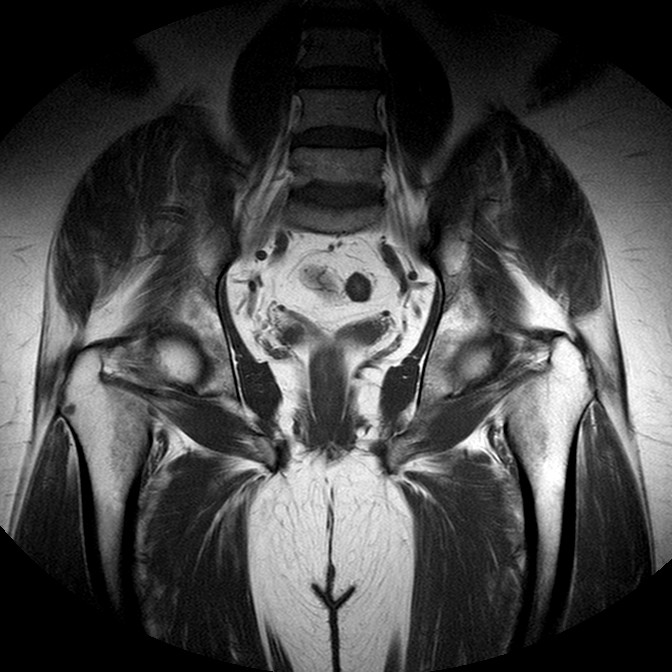

Esami: RMN BACINO

T1w TSE

Evidenti e simmetriche alterazioni osteofitosiche in regione coxo femorale con riduzione delle rime articolari. Degenerazione completa del cercine glenoideo. Non attuali segni di versamento articolare. Non segni di edema osseo che escludono attuale algodistrofia od osteonecrosi. Lieve e simmetrica riduzione del trofismo della muscolatura glutea.